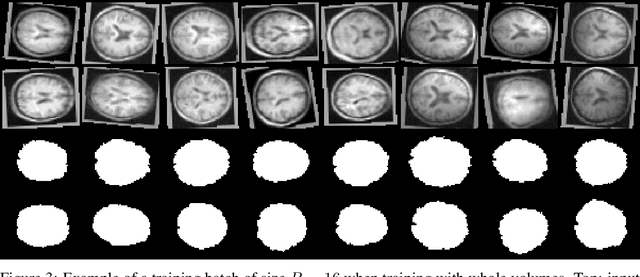

We present TorchIO, an open-source Python library for efficient loading, preprocessing, augmentation and patch-based sampling of medical images for deep learning. It follows the design of PyTorch and relies on standard medical image processing libraries such as SimpleITK or NiBabel to efficiently process large 3D images during the training of convolutional neural networks. We provide multiple generic as well as magnetic-resonance-imaging-specific operations for preprocessing and augmentation of medical images. TorchIO is an open-source project with code, comprehensive examples and extensive documentation shared at https://github.com/fepegar/torchio.